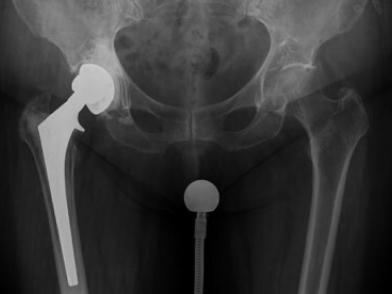

Ωστόσο, όπως και με οποιαδήποτε άλλη πρόθεση, η ολική αρθροπλαστική του ισχίου μπορεί να υποστεί διάφορες μορφές μηχανικής ή βιολογικής αποτυχίας. Μια τέτοια αποτυχία μπορεί να οδηγήσει σε μια νέα επέμβαση για την αντιμετώπιση της. Η επανεπέμβαση μετά από ολική αθροπλαστική ισχίου ονομάζεται αναθεώρηση του ισχίου.

Κατά τη διάρκεια της επέμβασης, ο χειρουργός μπορεί να χρειαστεί να αφαιρέσει ή να αντικαταστήσει ένα ή περισσότερα μέρη από την αρθροπλαστική. Τα μέρη που δεν είναι προσκολλημένα στο οστό μπορούν να αντικατασταθούν με ασφάλεια με ελάχιστη ή και καθόλου αφαίρεση του οστού. Ωστόσο, αν χρειαστεί να αλλάξουν τα μέρη που είναι σε επαφή με το οστό, μπορεί να προκύψει απώλεια οστού. Επιπλέον, κάποιοι από τους μυς γύρω από το ισχίο θα χαθούν, επηρεάζοντας έτσι τη δύναμη του ισχίου και τη λειτουργία του ασθενούς μετά τη χειρουργική επέμβαση. Τα αποτελέσματα της αναθεώρησης της επέμβασης δεν είναι τόσο προβλέψιμα όσο εκείνα της αρχικής επέμβασης. Οι επιπλοκές είναι πιο συχνές.

Η αναθεώρηση του ισχίου είναι μια δύσκολη και απαιτητική χειρουργική επέμβαση σε σύγκριση με την αρχική επέμβαση. Τα αποτελέσματα της χειρουργικής επέμβασης είναι λιγότερο προβλέψιμα από αυτά της αρχικής αρθροπλαστικής. Η διάρκεια της χειρουργικής επέμβασης είναι μεγαλύτερη και η πιθανότητα επιπλοκών υψηλότερη από ότι η αρχική αντικατάσταση του ισχίου. Για αυτό το λόγο οι αναθεωρήσεις πρέπει να γίνονται από πολύ έμπειρους χειρουργούς σε νοσοκομεία με άρτιο και τελυταίας τεχνολογίας εξοπλισμό.